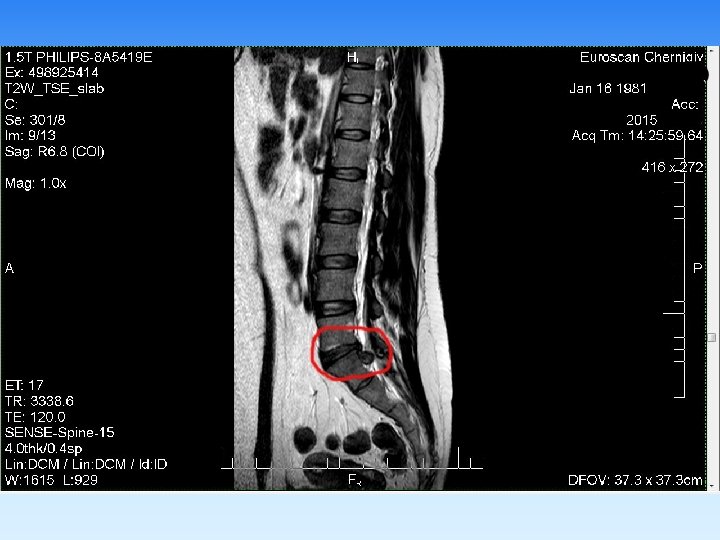

Примеры визуализаций

§ В неврологической практике МРТ позволяет диагностировать аномалии развития, воспалительные, дисциркуляторные, неопластические процессы головного и спинного мозга, а также его оболочек. Кроме того, незаменимым метод является в диагностике патологии межпозвонковых дисков, паравертебральных мягких тканей, а также в скрининговой диагностике патологии сосудов головы и шеи. § В ортопедии МРТ показано при любой патологии гиалинового хряща, внутрисуставных связок, менисков, ротаторной манжеты плечевого сустава, синовиальных складок, что позволяет достоверно диагностировать их разрывы, отек, инфильтрацию. § При исследовании брюшной полости МРТ позволяет диагностировать заболевания печени, желчевыводящих протоков (режим холангиографии без применения контраста обеспечивает визуализацию холедоха, вирсунгова протока на всем протяжении), поджелудочной железы, селезенки, надпочечников, лимфатических узлов брюшной полости. § Широко используется МРТ в гинекологии и урологии, в маммологии метод позволяет диагностировать объемные процессы и их распространенность.

Имеющийся у нас набор катушек томографа PHILIPS Ahieva позволяет визуализировать с высоким качеством: § головной мозг (в т. ч. аномалии гипофиза, с применением контрастирования); § артерии и вены головного мозга; § орбиты и зрительные нервы; § все отделы позвоночного столба; § тазобедренный, коленный, плечевой, локтевой, височнонижнечелюстной, суставы; § лучезапястный сустав , запястно-пястный отделы кисти, стопы и голеностопные суставы; § почки и надпочечники; § печень, поджелудочную железу, селезенку; § предстательную железу, яички, мочевой пузырь, матку, яичники: § мягкие ткани тела.